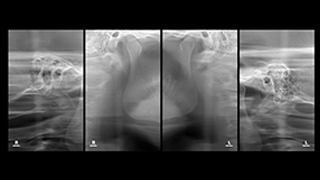

04 턱관절 검사

05 정면 X-ray 촬영

웃는얼굴치과의 12단계 교정진단시스템은 환자의 치아와 턱 구조,

얼굴 균형, 교합 상태 등을 체계적으로 분석하여

최적의 치료 계획을 수립하는 첨단 진단 프로세스입니다.